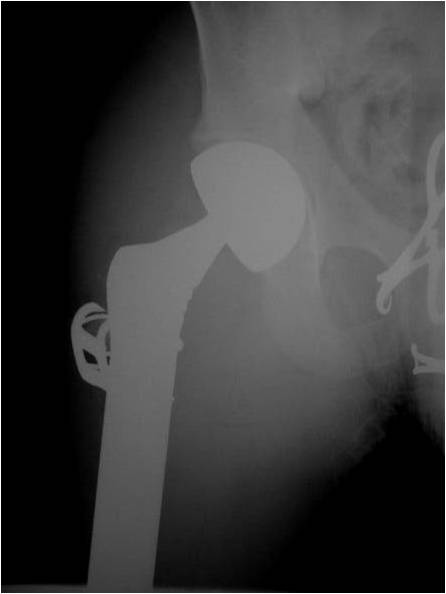

- Femur: Single most common site

Radiographic Presentation

- Permeative or moth eaten bone destruction

- Ill defined and malignant appearing

- Bony changes are often subtle

- Soft Tissue Mass in 90% of of cases

- Periosteal Reaction in 50% of cases

- Onion Skin (colic pattern of irritation)

- Hair on End (rapid continuous lifting of periosteum)

- Reactive Bone Sclerosis is rare but occurs in 10% of cases

- No cartilage or bone production by tumor

- Pathologic fracture in 10-15%